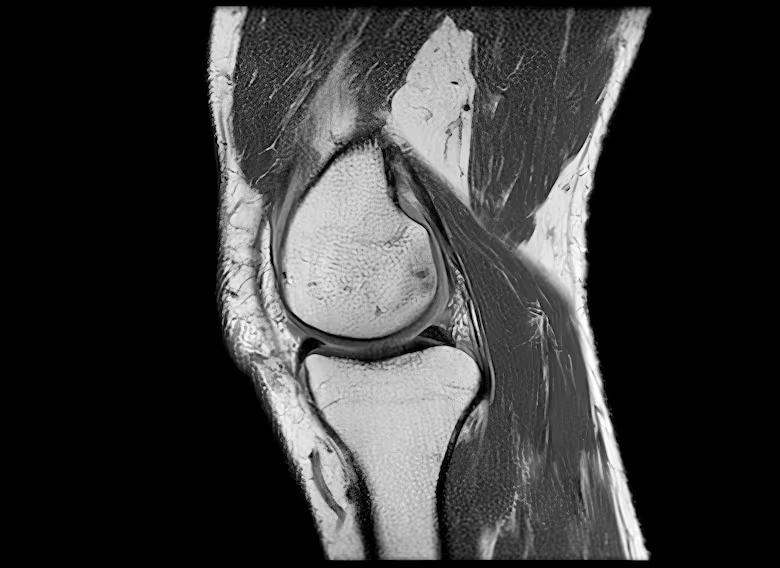

“La rodilla es una de las articulaciones más complejas de todo el cuerpo”, explica a la BBC Anikar Chhabra, cirujano ortopédico especializado en medicina deportiva de la Clínica Mayo, en Phoenix (EE. UU.).

Las rodillas dependen de cuatro grupos musculares que son los isquiotibiales, glúteos, cuádriceps y pantorrillas. Ellos les dan estabilidad y capacidad de absorción. Añade Chhabra:

«Cuando esos músculos no están interactuando y trabajando juntos, la articulación recibe más presión. Ahí es cuando comenzamos a sentir el dolor»

Asimismo, los estudios muestran que fortalecer estos músculos mediante el ejercicio puede prevenir la degeneración del cartílago, retrasar la osteoartritis e incluso evitar una cirugía de reemplazo. Mantenerlos fuertes también reduce la carga sobre la rodilla y el dolor en quienes ya presentan síntomas iniciales.